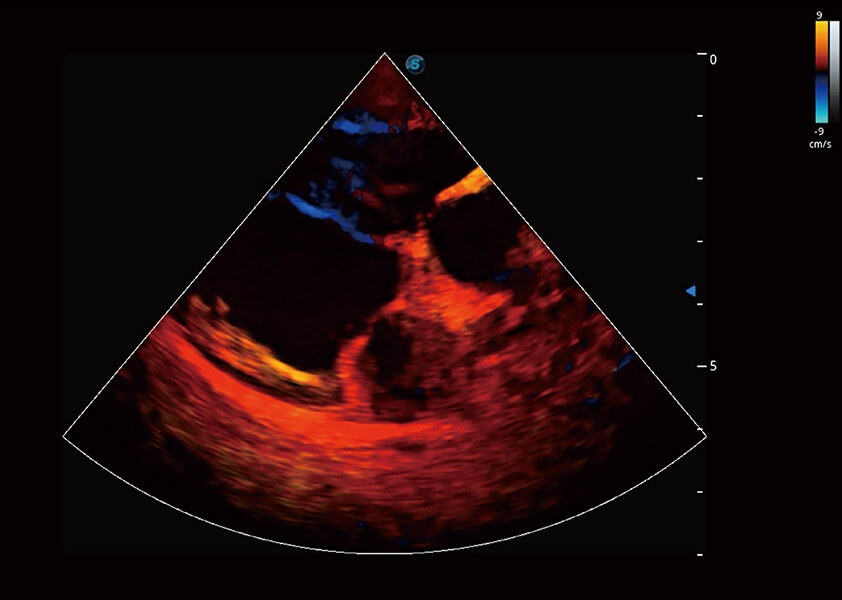

ProPet 60 作为一款高端台式动物超声设备,为动物医生的日常诊断提供了一系列贴合动物临床需求、解决临床实际问题的高级成像功能。凭借全系列高清探头,满足医生对腹部、心脏、生殖、浅表、肌骨等成像的所有需求,切实帮助您提升检查效率,提高诊断信心。

动物是人类最亲密的朋友和最值得信赖的伙伴。新葡的京集团8814检测站也一直致力于探索动物专用的超声影像解决方案。 全新推出的ProPet系列,是新葡的京集团8814检测站在动物超声影像智能化、专业化、精准化的一次跨越式革新。动物不能用言语来表述自己的不适,通过超声影像,ProPet系列搭建了动物医生与不同物种沟通的“桥梁”,为动物医生注入了“治愈之力”。